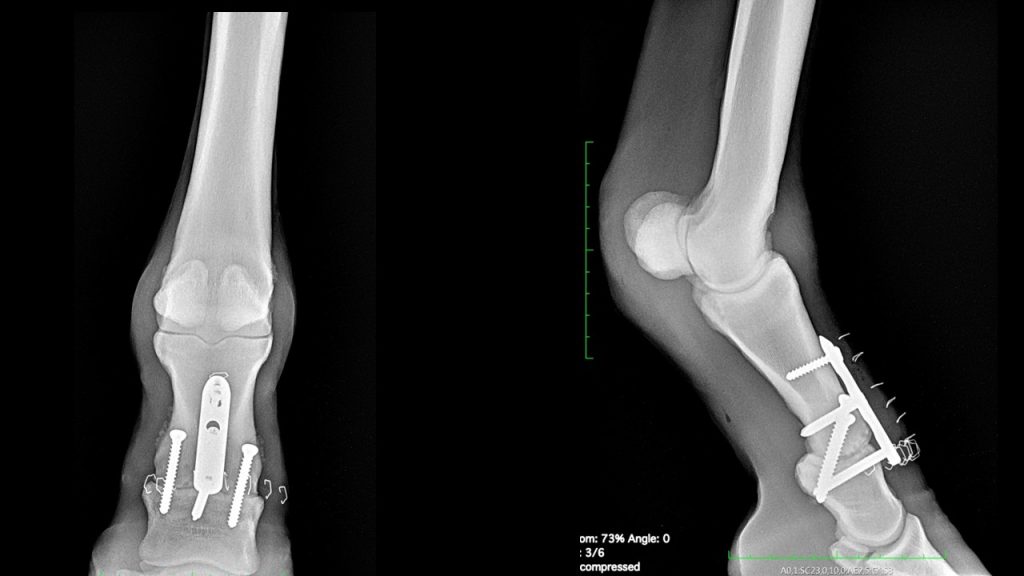

繋関節の固定には関節を開いて、関節軟骨を掻把して、関節が曲がらないようにプレートとスクリューで圧着する方法があります。(右図)

この馬は、来院した時点でかなり関節周囲に骨の増殖が起きており、肢も曲がらない状態に近かったので、より侵襲の少なく、早く関節固定できる手術方法を選択しました。

親愛なるDr.Ducharme先生の論文。 ほぼ動的に動きのなくなった関節に対し、太い針を刺して、そこからレーザーを挿入して関節内を焼灼します。

利点は

① 従来の方法より侵襲が明らかに少ない

② 痛覚神経を失活させるため術後に極めて早期の痛覚消失に繋がる

③ 関節軟骨表面と滑膜の炎症細胞を減少させる

レーザーで関節内を焼灼した後に、関節内をまたぐScreweを挿入します。